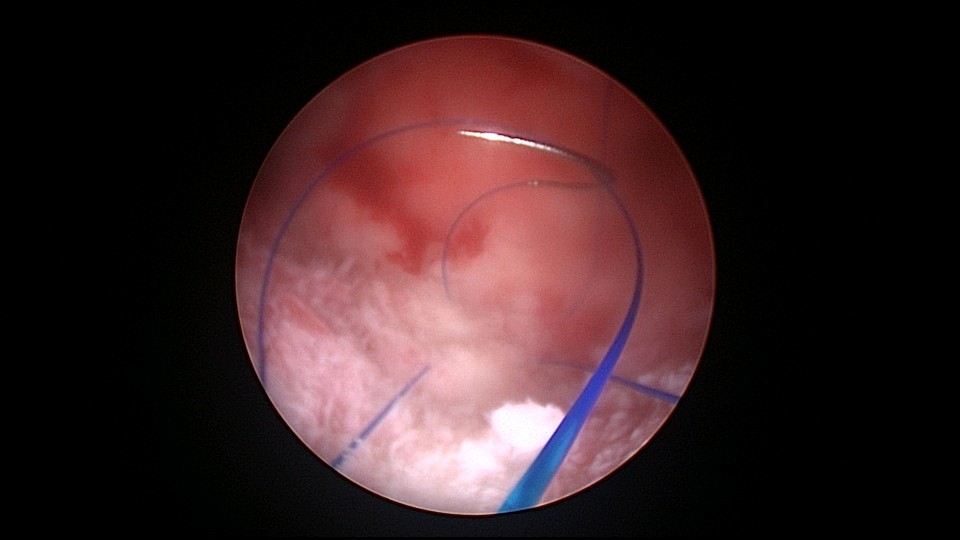

患者38岁,G4P2,剖宫产2次。2025年4月,停经40+天,计划外妊娠,要求终止妊娠并放置节育环,考虑终止妊娠后宫腔大,担心环移位或脱落,要求固定节育环。4-0不可吸收线将节育环缝合固定于宫腔上段后壁,缝合2针形成线圈固定节育环,没有打结推结。利用子宫肌层的卡压,缝合线圈不会自动松脱,形成有效固定,宫颈外口剪断线尾,留线较长,更利于固定。